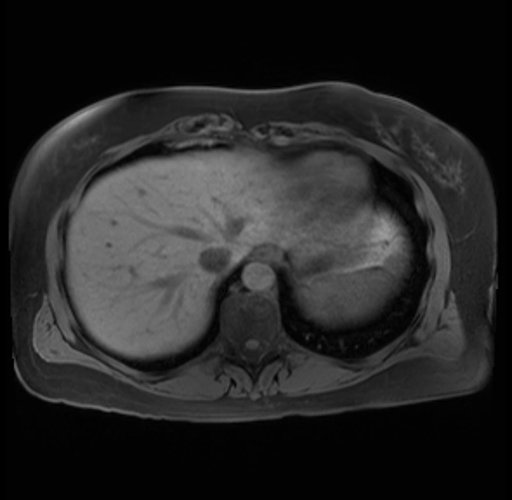

Imaging Analysis

Look through the patient's CT scan to identify any areas of concern for the necessary procedure.

Based on your CT findings, which issue(s) are present and would give reason for "planned slowing down moment(s)" in this case?

Considering a standard distal pancreatectomy procedure, what step(s) of the operation would you do differently in this case?